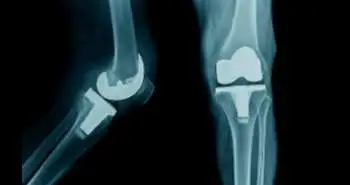

With PFA, there is greater possibility of patients returning to the operating room for revision and conversion to TKA.

The Hospital for Special Surgery, New York, presents a report according to which the chances of revision and conversion are higher among people who received Patellofemoral arthroplasty (PFA) than total knee arthroplasty (TKA). To treat the last stage, isolated patellofemoral arthritis (PFOA), TKA and PFA are the accepted therapies but with a different rate of re-operations and complications.

The PFA and TKA group showed 6.34 and 0.11 weighted rate of either conversion or revision arthroplasty. Further, the weighted rate of return to the OR and manipulation under anaesthesia (MUA) noticed for soft and bony tissue procedures was (0.79 and 1.06) and (1.23 and 0.32), respectively. These findings reflect that TKA therapy associated with fewer chances to return to the operating room as compared to the PFA.